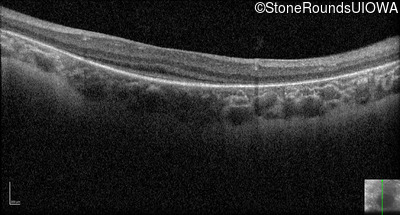

Optical Coherence Tomography - Right - No Light Perception

Exemplar / OCT Stack